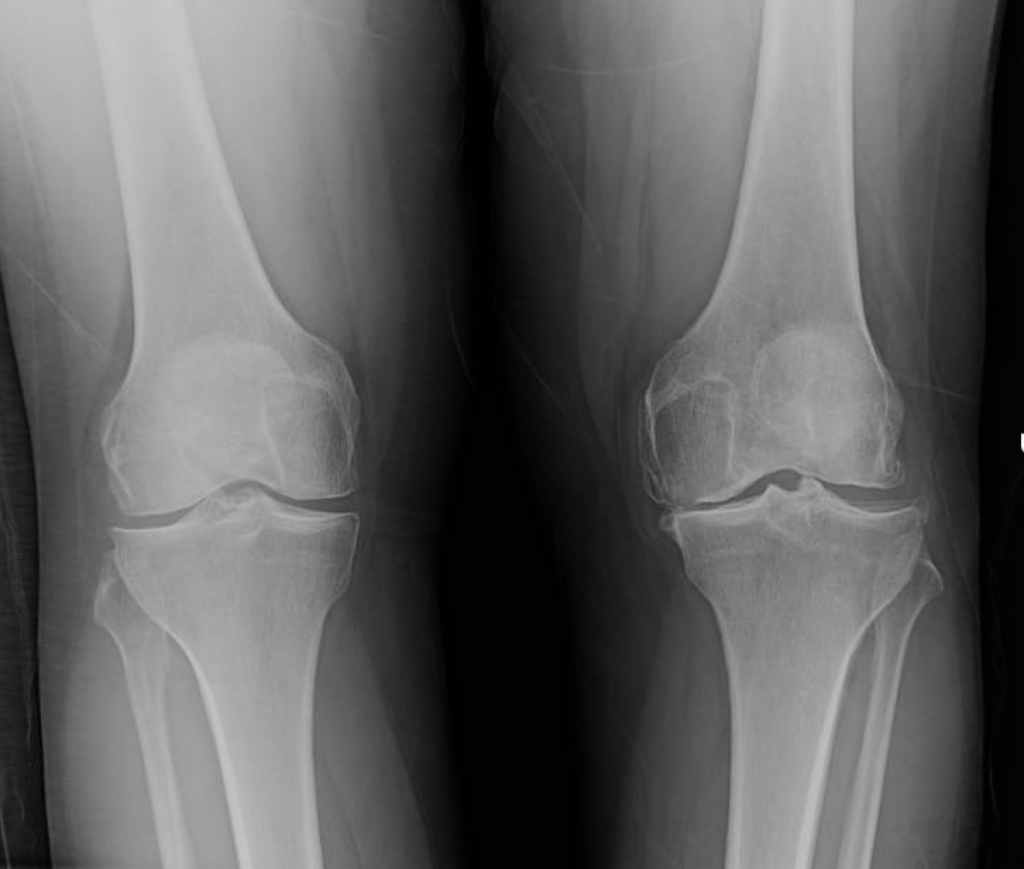

This is a 56 year old female with severe post-trauamtic arthritis of the left knee. She underwent prior knee arthroscopy, which failed. She had continuous pain, a significant limp, and a flexion contracture of 15 degrees.